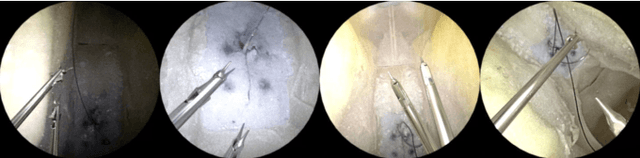

Abstract:Surgical robots are controlled using a priori models based on robots' geometric parameters, which are calibrated before the surgical procedure. One of the challenges in using robots in real surgical settings is that parameters change over time, consequently deteriorating control accuracy. In this context, our group has been investigating online calibration strategies without added sensors. In one step toward that goal, we have developed an algorithm to estimate the pose of the instruments' shafts in endoscopic images. In this study, we build upon that earlier work and propose a new framework to more precisely estimate the pose of a rigid surgical instrument. Our strategy is based on a novel pose estimation model called MBAPose and the use of synthetic training data. Our experiments demonstrated an improvement of 21 % for translation error and 26 % for orientation error on synthetic test data with respect to our previous work. Results with real test data provide a baseline for further research.